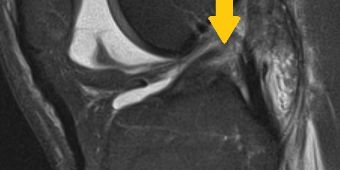

mr-schnitt-kreuzbandruptur

MRT des Kniegelenks mit weißem Gelenkerguß und Kreuzbandriß (Pfeil). © Asklepios

Das Knie wird durch wichtige Bandstrukturen, die im und außerhalb des Gelenks verlaufen, stabilisiert. Wenn ein Band durch einen Unfall reißt, verliert das Gelenk seinen Halt und die Scherkräfte nehmen zu. Dadurch wird der Gelenkknorpel geschädigt und es entsteht langfristig ein schmerzhafter Gelenkverschleiß. Deshalb muss die Stabilität des Gelenks zügig wieder hergestellt werden, um eine mechanische Überlastung des Knorpels zu verhindern. Je nach verletzter Bandstruktur stehen dabei verschiedene Behandlungsmöglichkeiten zur Verfügung.

• Kreuzbänder: das vordere Kreuzband kann bei Unfällen, bei denen das Knie verdreht wird, reißen (Bild oben). Gerade bei jungen und sportlich aktiven Patienten sollte das Band unbedingt rekonstruiert werden, da im instabilen Gelenk sonst weitere Folgeschäden auftreten können. Je nach Art der Ruptur muss das Band deshalb genäht oder auch durch eine körpereigene Sehne ersetzt werden. Reißt das Band bei einem schweren Unfall erneut, gibt es auch weitere Techniken, um das Band ein zweites Mal zu rekonstruieren. Das hintere Kreuzband reißt dagegen wesentlich seltener und kann in vielen Fällen durch seine gute Durchblutung konservativ mit speziellen Schienen und Nachbehandlungsprogrammen behandelt werden. Gerne beraten wir Sie über die verschiedenen Behandlungsmöglichkeiten.